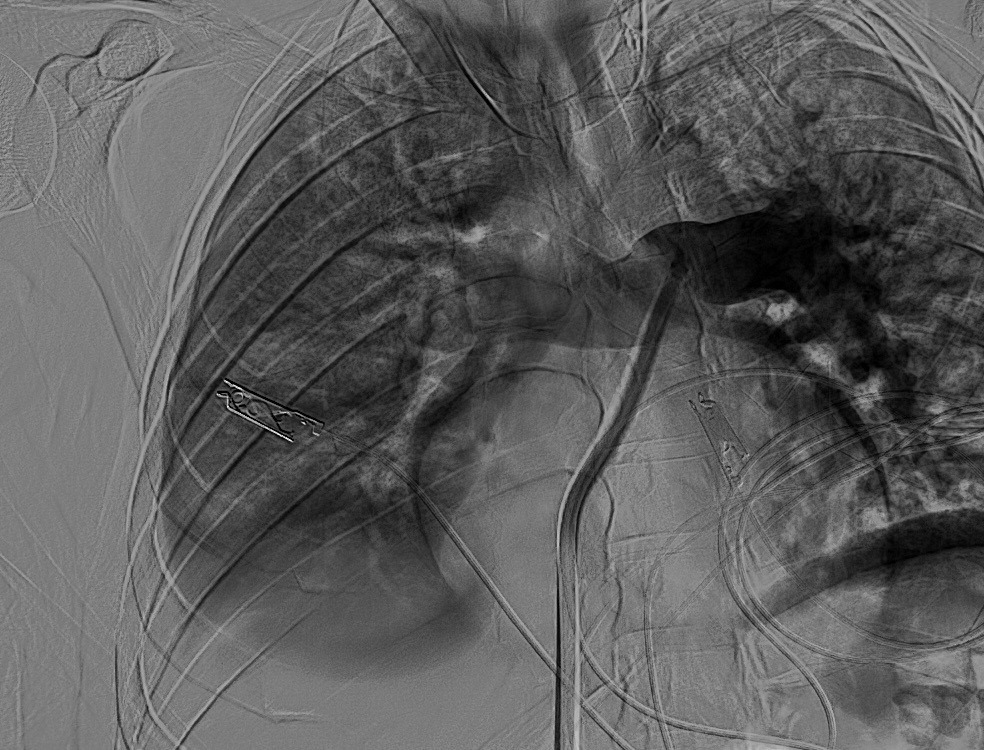

سجل مجمع الدمام الطبي أحد مكونات تجمع الشرقية الصحي ، إنجازاً طبياً نوعياً بعد نجاح فريق الأشعة التداخلية في إنقاذ حياة مريض كان يعاني من جلطة رئوية حادة وكبيرة شكّلت خطراً مباشراً على حياته ، وذلك باستخدام تقنية طبية متقدمة دون الحاجة إلى جراحة قلب مفتوح .

وكان المريض قد نُقل بشكل إسعافي من أحد المستشفيات وهو في حالة حرجة ، نتيجة معاناته من ضيق شديد في التنفس وانخفاض حاد في مستوى الأكسجين ، إثر انسداد كامل في الشريان الرئوي الرئيسي بسبب خثرات وريدية عميقة ظهرت بعد خضوعه لعملية منظار لمفصل الركبة.

وبفضل سرعة الاستجابة وجاهزية فريق الأشعة التداخلية جرى التدخل العلاجي العاجل وفتح الشريان الرئوي وسحب الجلطة بالكامل بدقة عالية ، ما أدى إلى تحسّن فوري في العلامات الحيوية واستقرار الحالة دون تسجيل أي مضاعفات.